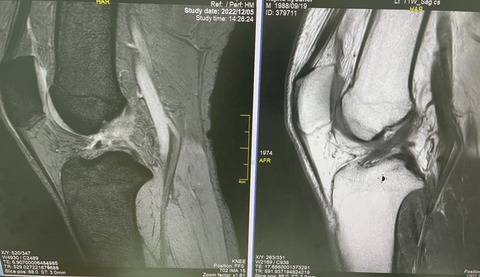

34歳、フットサル 愛好家選手

プレイ中に受傷。

MRIで、膝前十時靭帯損傷あり、不安定性も認める

受傷時